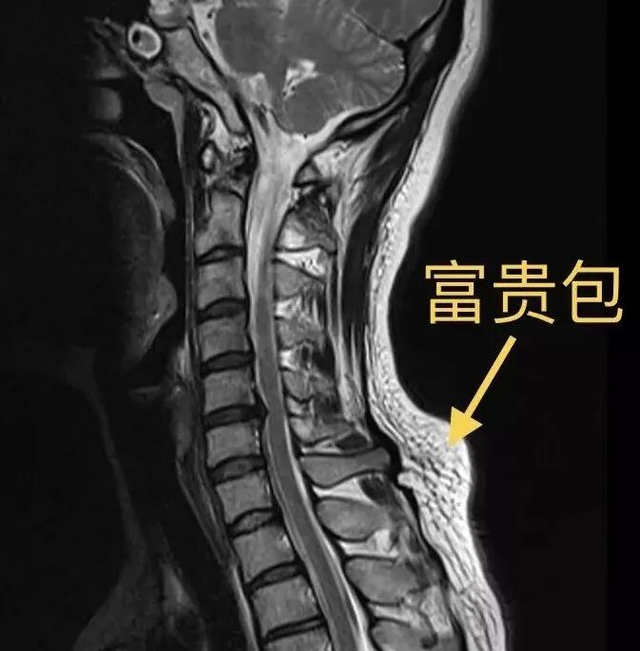

“富贵包”又称为富贵背,是颈椎和胸椎交界处突出的一个硬包块。颈部大包中既有增生的软组织,也包括骨骼(椎体棘突)的突出和脂肪化的肌肉组织。

第七颈椎(颈椎的最后一节,也是颈椎与胸椎的交界处)本身棘突较长。

我们正常的颈椎应该是前突,而胸椎应该是后突,在这个交界处,如果颈椎和胸椎都过度突起,那么就会让相关的肌肉群紧张痉挛而肿胀。

所以当原本就凸起的“第七颈椎棘突”遇到颈胸交界处周围肌肉群紧张肿胀时。

“富贵包”

一个外观似颈后大包的向后凸起

也就慢慢形成了